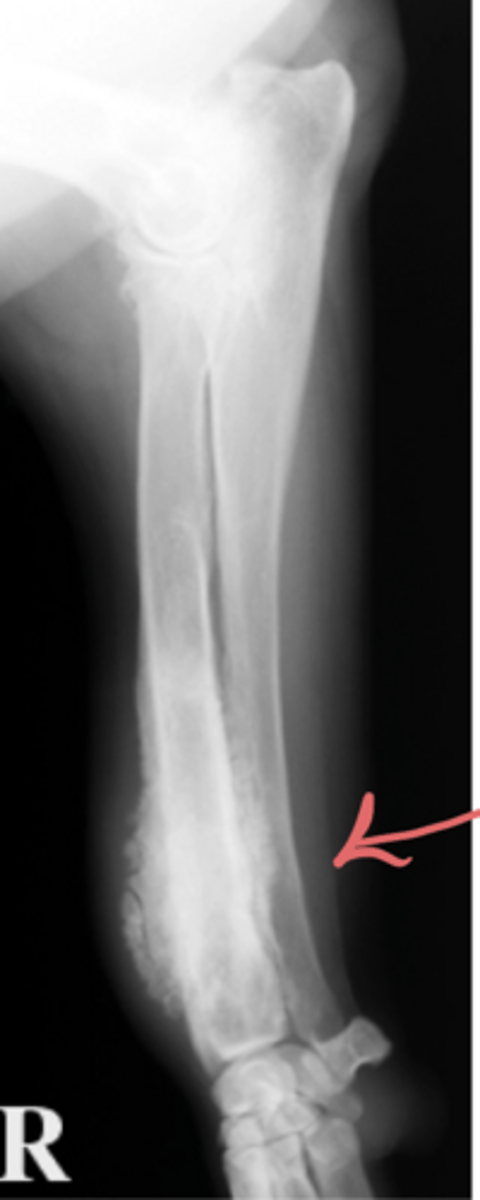

What are signs of non- erosive joint lesions?

Osteophyte

Identify the pathology?

Enthesiophyte